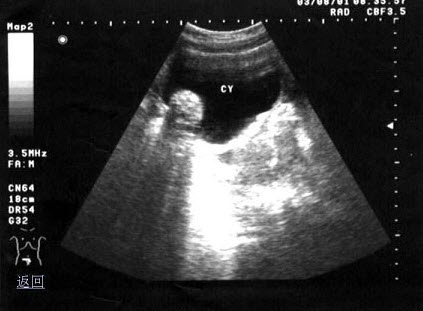

D.②③④⑤⑥

E.①⑤⑥

44、单项选择题 轴(纵)向分辨力直接与什么有关()

A.穿透深度